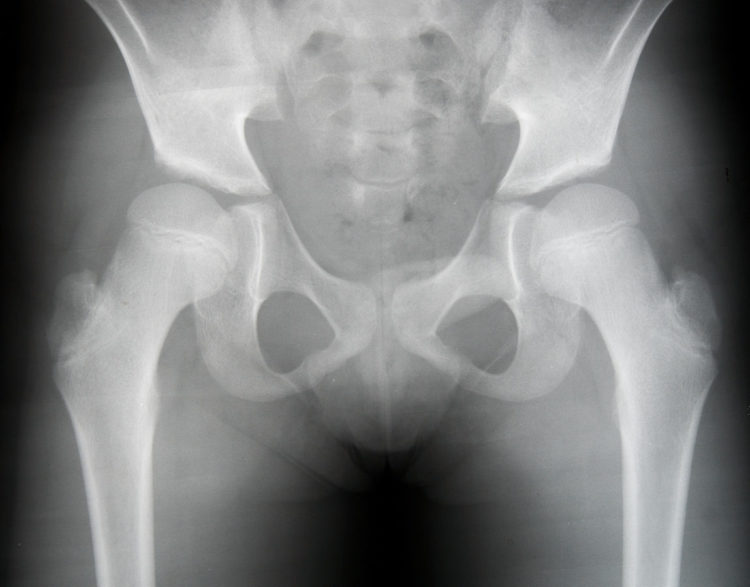

La dysplasie de la hanche peut être détectée par une échographie avant l'âge de trois mois, ou par une radiographie après cet âge. Facteurs de risque de la dysplasie de la hanche. Cette condition est causée par plusieurs facteurs, à la fois une prédisposition génétique et des facteurs mécaniques intrinsèques et extrinsèques.

La radiographie de la hanche Analyses Soignezvous